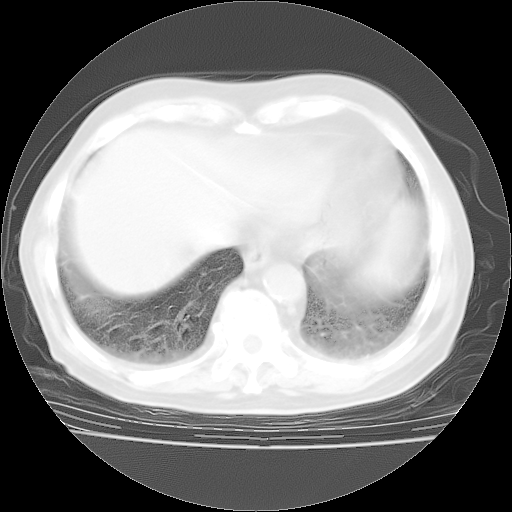

4月28日肺部CT

个人阅读4.14日肺部CT平扫:纵隔窗无异常,但肺窗示:双下肺内、后基底段有片絮状侵润影,部位以后基底段为著,以间质改变为主,呈急性肺泡炎征像,和首次住院影像学有相似之处。仅是个人读片,明日请相关专家再读片哈。其它建议同上。

1、108#的是4月14日的胸部CT(发此贴时还没看着28日的CT)。14日的胸部CT其实已经出现改变(如108#所述),个人认为28日的胸部CT除纵膈窗疑似有双侧胸膜增厚或少量胸积液(可行胸部B超明确)外,与4月14日对照病变有所加重;2、已经给予“异烟肼、利福平、乙胺丁醇”抗痨治疗?如果是,甲强龙80mg可缓慢减量;如果环磷酰胺已停用,暂不使用;3、中性粒细胞92%,明显升高,目前体温情况?注意合并细菌感染可能,使用左氧氟沙星情况下,是否联用B-内酰胺类抗菌药物?另外是查免疫全套非风湿全套。

今请临免主任会诊后认为:4月14日胸部CT已有双下肺间质性改变。患者病情复发多系激素减量过快不正规所致。目前甲强龙80mg/日,一周后酌情开始减量,不易过快。环磷酰胺若已停用,暂不使用。他同意目前抗菌药物使用,但应考虑是否加用B-内酰胺类抗菌药物(中性细胞明显增高);2、结核复发目前依据不足;3、若免疫全套各项指标正常,考虑多系特发性肺间质炎可能大。4、加强支持,并注意保护胃黏膜。

今上午去请教了临免、呼吸主任:1、介绍病史和阅读系列胸部CT一致认为:患者肺结核不考虑,仍为肺间质纤维化,目前处于急性肺泡炎阶段。2、若仍发热,可将甲强龙增至:80mg Bid静滴,同时鉴于中性增高,合并细菌感染可能,继续左氧氟沙星治疗,再联用B-内酰胺抗菌药物,如头孢哌酮--舒巴坦;3、停用抗痨药;4、目前甲强龙每日剂量160mg ,体温正常后再酌情减量;目前暂不用免疫抑制剂;4、不建议使用免疫增强剂等;5、加强支持治疗,鼓励患者进食;5、注意随访肝、肾功及血常规情况;6、因患者目前激素用量较大,加用胃黏膜保护剂,防止消化道出血可能。